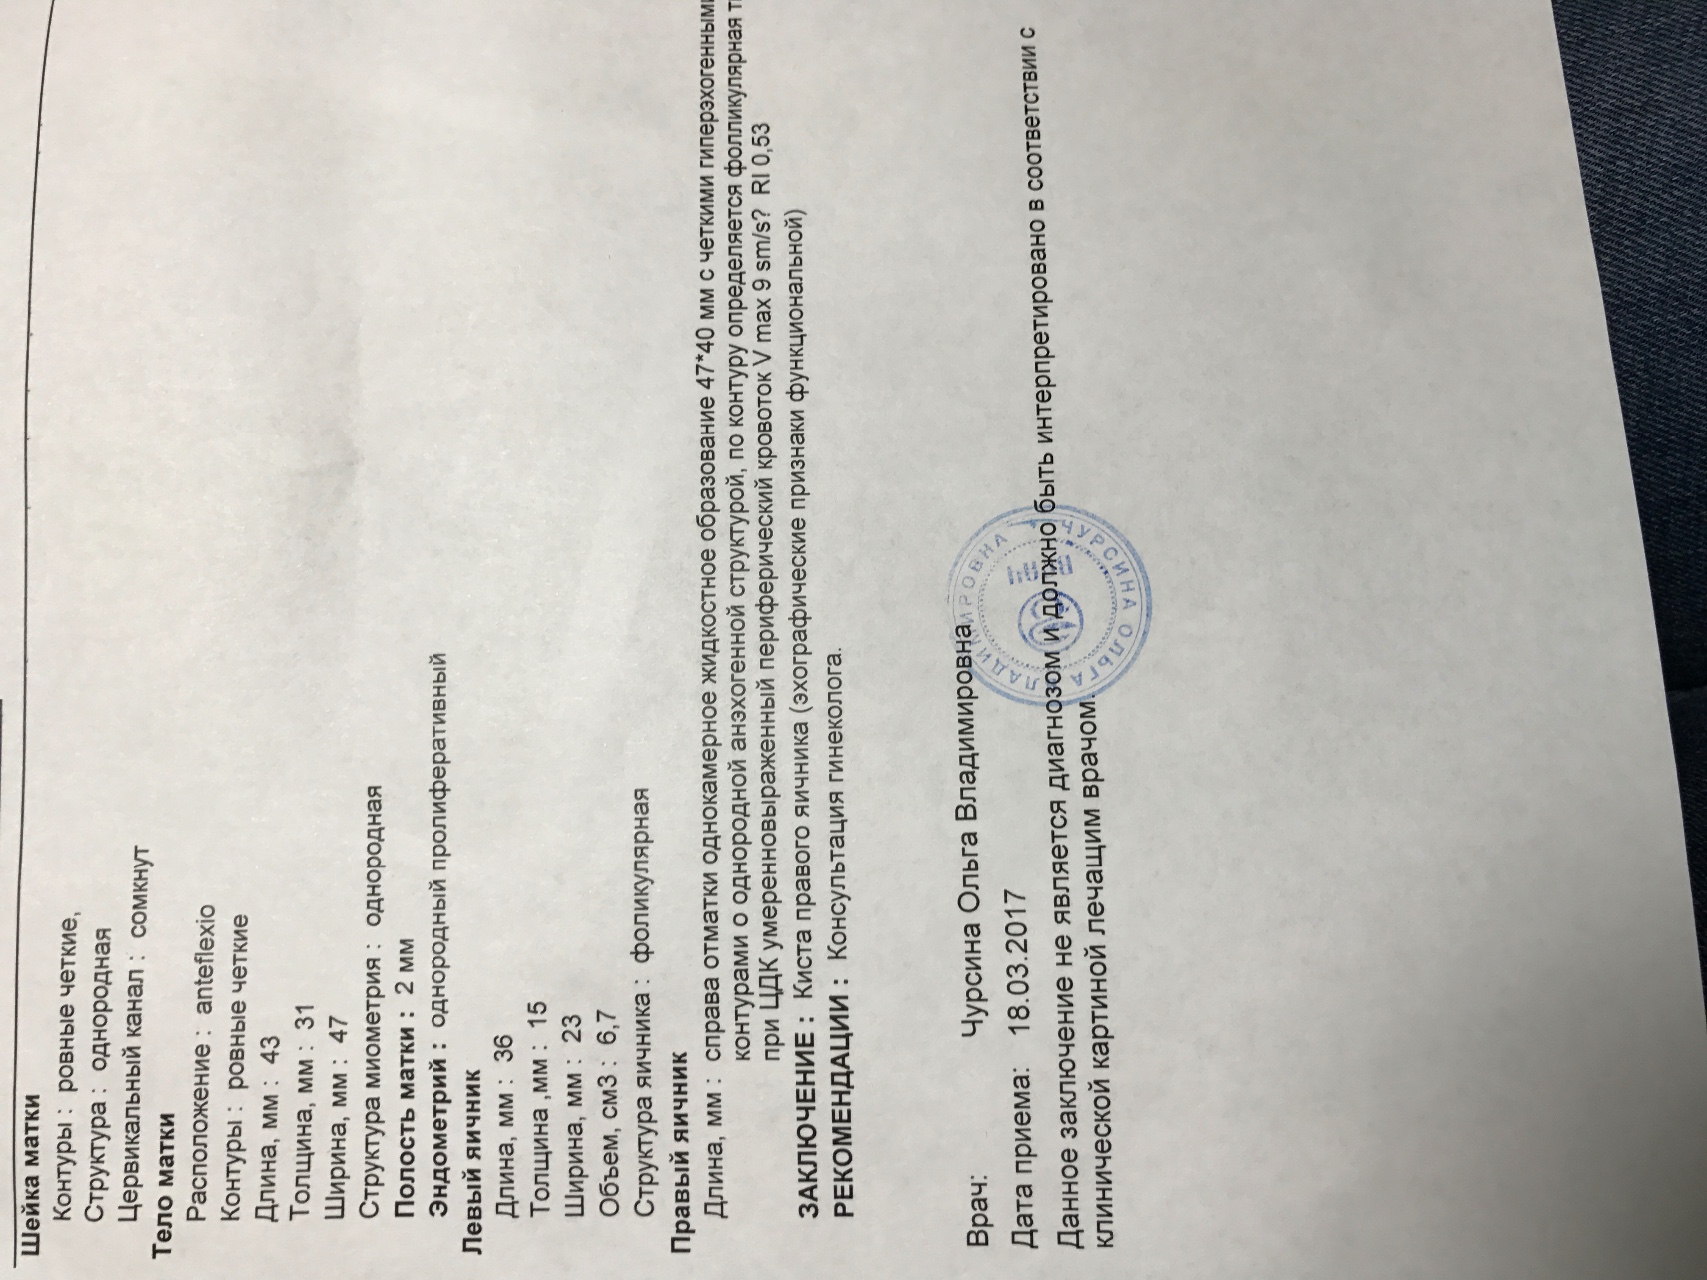

Гистологические изображения фолликулярной кисты яичника